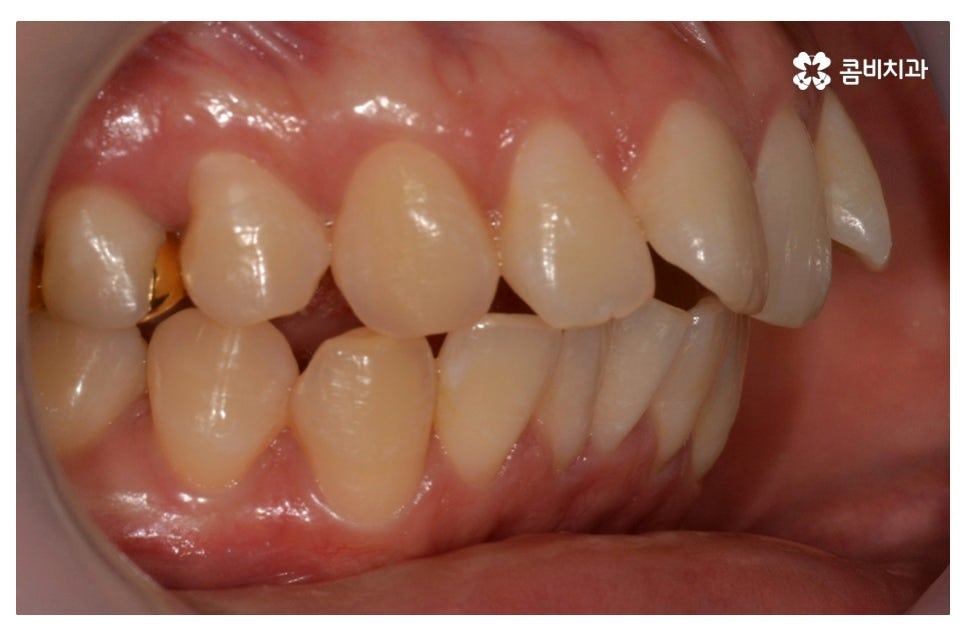

덧니교정은 개인에 따라서 치료 계획이 달라질 수 있는데

덧니의 정도가 사람마다 다르고 구강 구조, 얼굴형, 교합 등을

종합적으로 파악하여 치료 계획을 세울 필요가 있어요.

덧니로 인해 고민하는 분들 중에서 돌출입을 개선하고자

하는 분들도 많고 부정교합이 있는 분들도 많기 때문에

치아의 이동 공간과 치아 이동으로 인한 얼굴 변화, 교합 등에

대해서 면밀한 파악이 중요하다고 할 수 있는데요.

이번 포스팅에서 보인 덧니교정 사례의 경우 기능이 적은 작은 어금니를

발치하여 교정이 진행되었으며 발치를 진행하는 경우

작은 어금니를 발치하는데 충치 등으로 인해 손상이 큰 치아를

발치하는 경우가 일반적이라고 할 수 있어요.